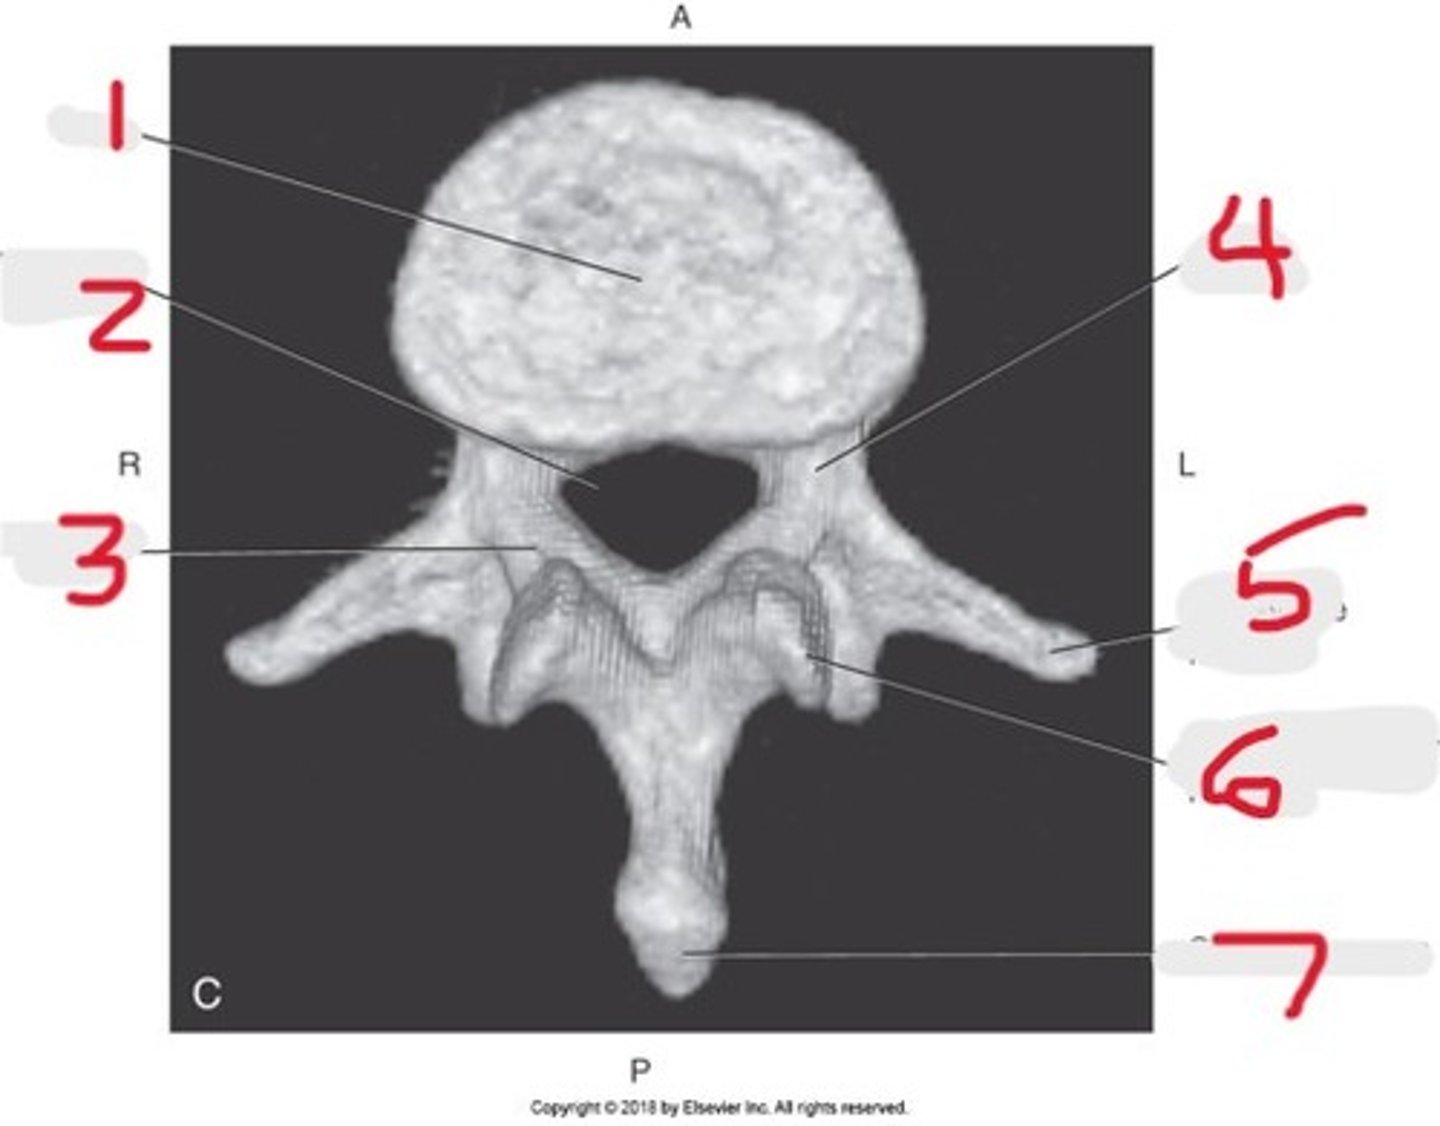

1) Body

2) Vertebral foramen

3) Lamina

4) Pedicle

5) Transverse process

6) Superior articular process

7) Spinous process

Name all numbered structures